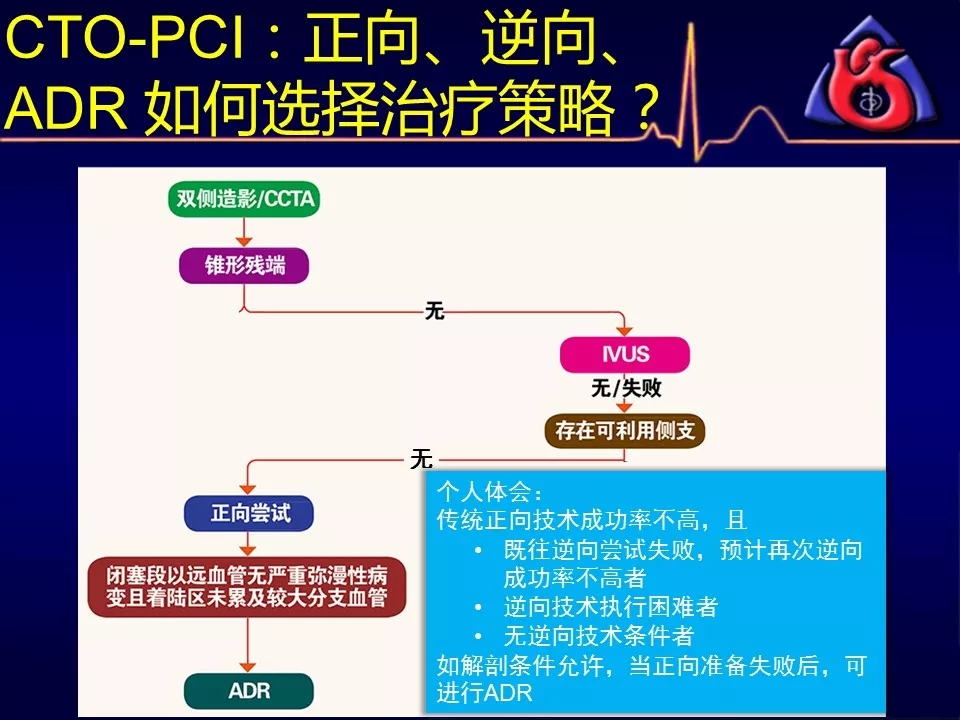

既往逆向技术尝试失败,再次逆向成功率不高者

当逆向技术困难时,如解剖条件许可,应优选ADR

逆向技术无条件(无可利用侧枝血管)